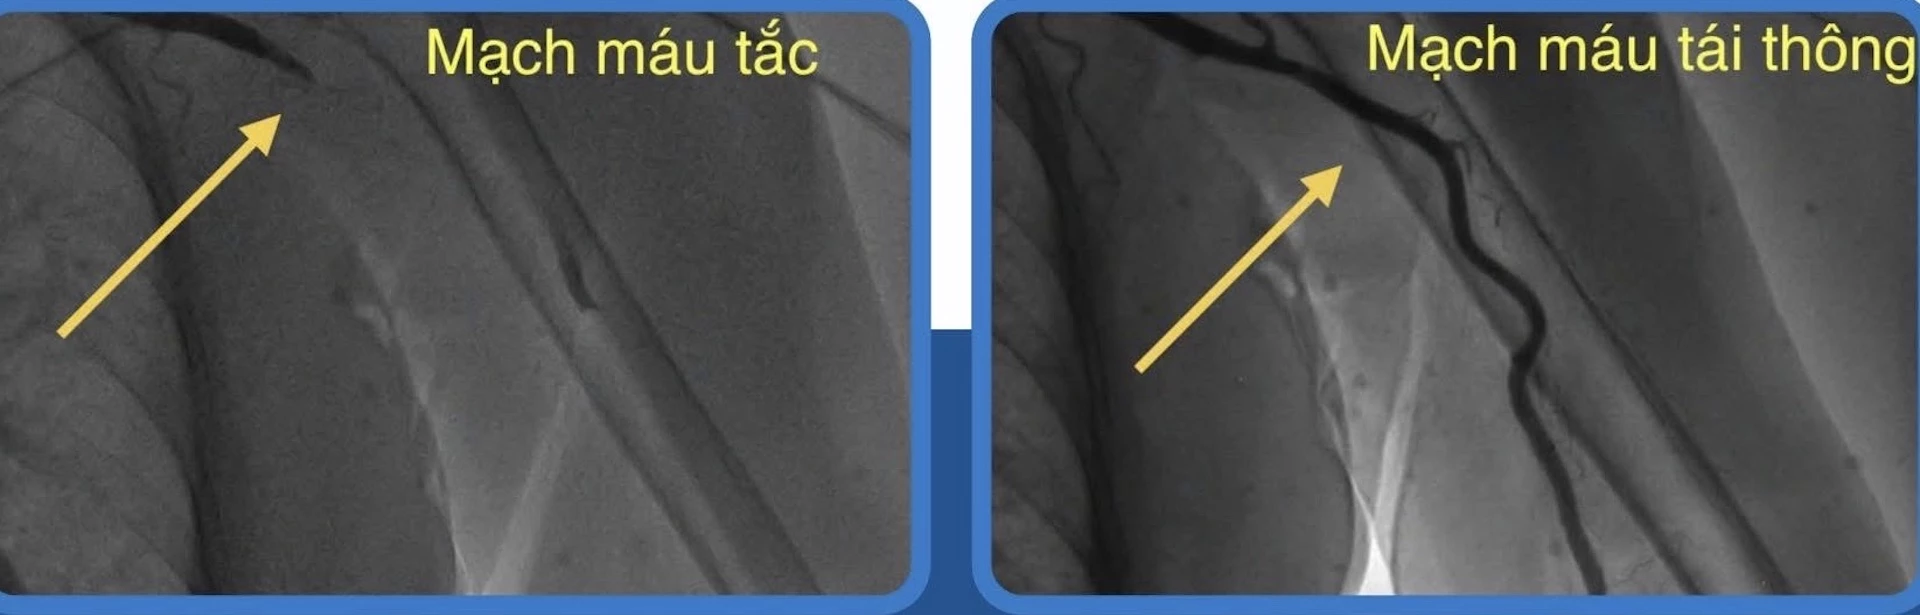

Trước tình trạng nguy kịch của bệnh nhân, ê-kíp bác sĩ Khoa Tim mạch can thiệp của bệnh viện đã nhanh chóng tiến hành chụp mạch và nong bóng khai thông động mạch cánh tay trái dưới hệ thống chụp mạch số hóa xóa nền. Sau can thiệp, dòng chảy của máu được khôi phục hoàn toàn đến vùng cẳng và bàn tay trái. Nhờ đó, các triệu chứng lâm sàng của bệnh nhân được cải thiện hoàn toàn, mạch tay rõ, bàn tay hồng hào, tay ấm trở lại.

| Hình ảnh trước và sau dòng máu được tái thông. |